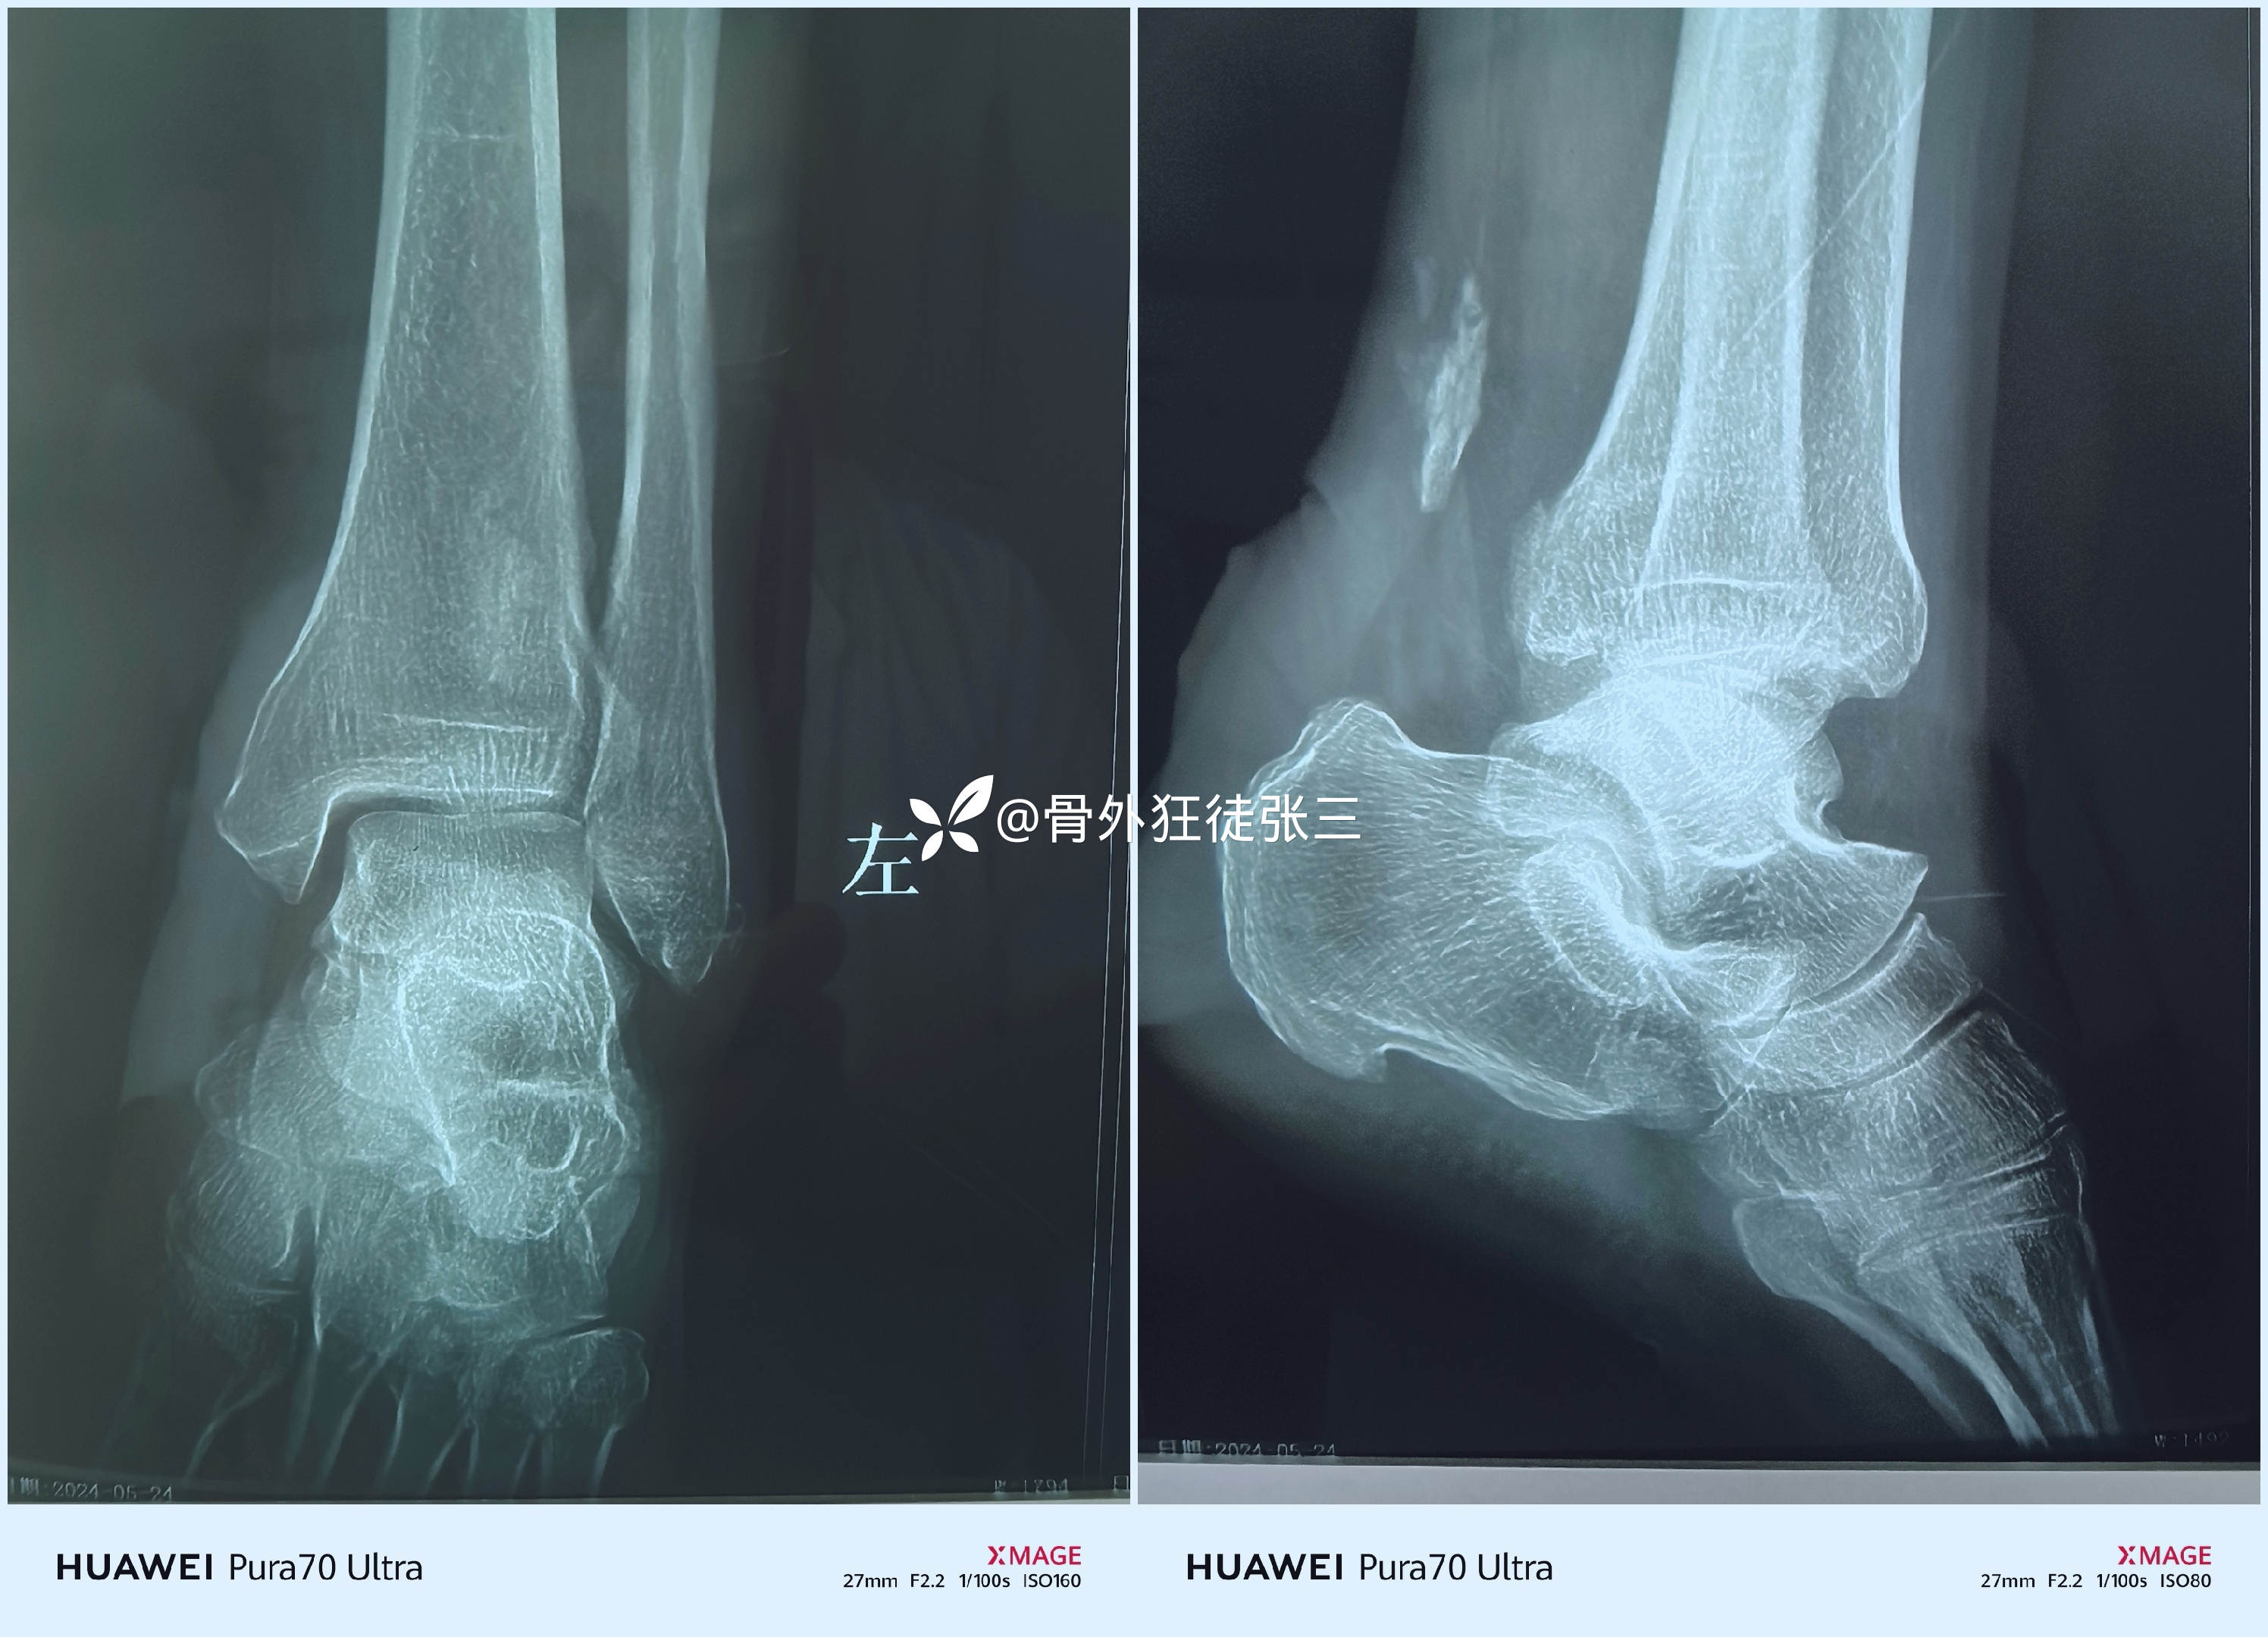

患者性别:男

患者年龄:65岁

主诉:摔伤左下肢致肿痛、畸形、活动受限3天。

一,X线

看似:风平浪静,水波不兴。

正位猛地一看

似乎没什么大问题

侧位一看

似乎只有后踝骨折

此时的你,信心满满,简单骨折,准备急诊手术,固定后踝,行吗?能吗?可以吗?